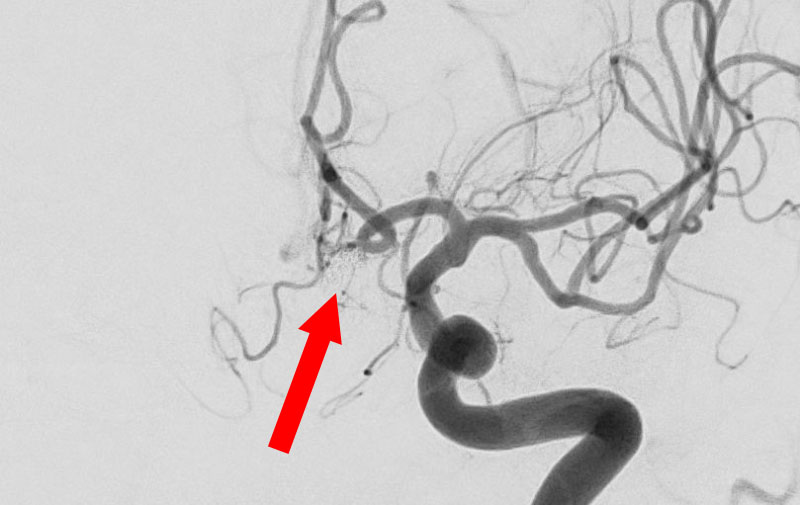

No.1596 手術前

くも膜下出血

左中大脳動脈瘤破裂

40代

救急外来